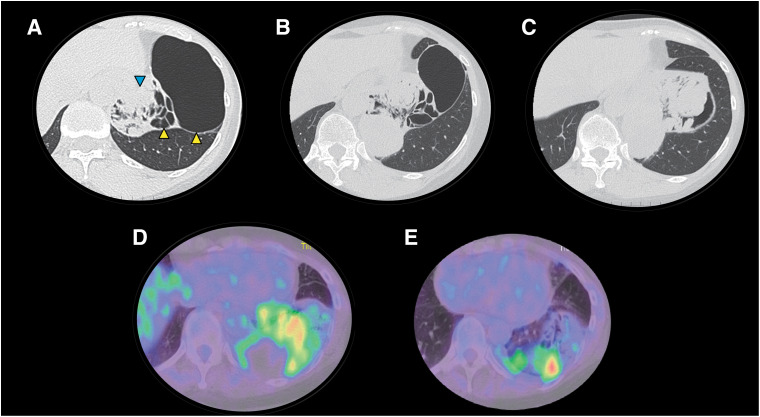

原发性肺肉瘤是一种罕见的疾病,在由肺囊肿引起的肿瘤中,其发病率远低于肺癌。我们报告一例女性患者在左侧S9-10表现出多灶性囊肿。随访CT显示囊肿有消退的趋势,但囊肿壁实性成分继续增厚,长成直径10 cm的肿瘤。行胸腔镜下左下肺叶切除术诊断和治疗肺囊性病变。肺囊性病变病理表现为非典型梭形细胞增生组成的实体瘤,伴支气管组织被困。根据影像学和病理表现,诊断为原发性肺肉瘤,起源于肺囊肿。本病例强调,即使出现肺囊肿缩小,如果观察到囊肿壁增厚,也应仔细随访并及时进行手术治疗。

Primary pulmonary sarcoma is a rare disease and is much less common than lung cancer among tumors arising from pulmonary cysts. We report the case of a female patient who showed multifocal cysts in the left S9-10. Follow-up computed tomography (CT) revealed that the cyst tended to regress, but the solid component of the cyst wall continued to thicken, growing to a 10-cm-diameter tumor. Thoracoscopic left lower lobectomy was performed to diagnose and treat the cystic lung lesions. For the pathology of the pulmonary cystic lesion, it was marked by solid tumors composed of proliferative atypical spindle cells, with some trapped bronchial tissue. Based on the imaging and pathological findings, the diagnosis was primary pulmonary sarcoma arising from the pulmonary cyst. The present case highlights that, even when a pulmonary cyst appears to shrink, careful follow-up and timely surgical consideration are warranted if cyst wall thickening is observed.